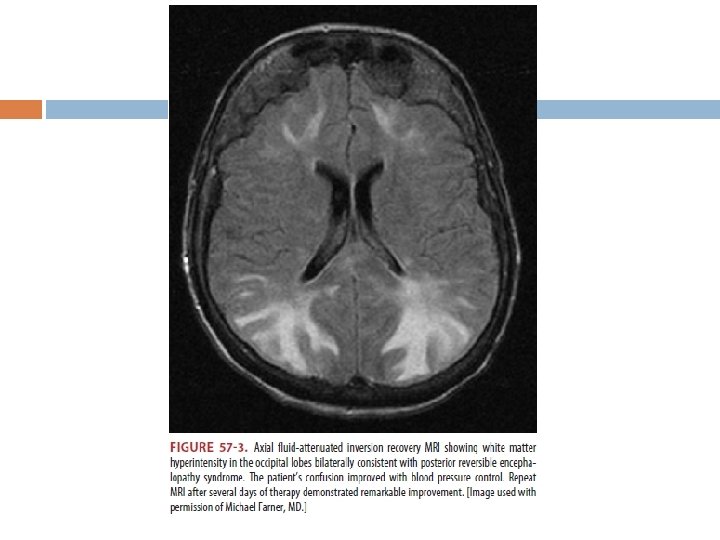

HİPERTANSİF ENSEFALOPATİ Kan basıncı yüksekliği ile beraber baş ağrısı, fokal nörolojik defisitler iskemik ya da hemorajik strok ile ilişkilidir. Akut iskemik strok tanısı MRI ile serebral hemoraji tanısı beyin BT ile konulur. Hipertansif Ensefalopati; fokal iskemi ve kanamayı dışladıktan sonra konan klinik bir tanıdır. � Kliniğinde; mental durum değişkliği, baş ağrısı, kusma, nöbet, görsel semptomlar ve birçoğunda papilödem vardır. � MRI’da eğer posterior bölgede fokuslanmış ödem varsa Posterior Reversible Ensefalopati Sendromu olarak bilinir.